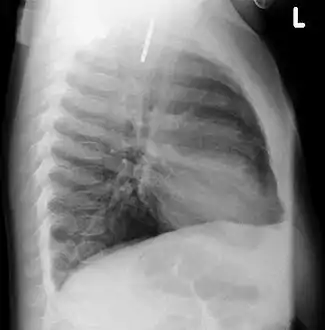

A coin seen on lateral CXR in the esophagus